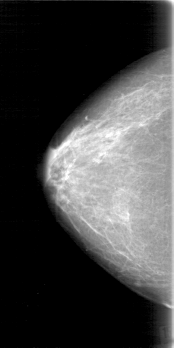

D_4024_1.RIGHT_MLO

RIGHT_CC LINES 5206 PIXELS_PER_LINE 2596 BITS_PER_PIXEL 12 RESOLUTION 43.5 NON_OVERLAY